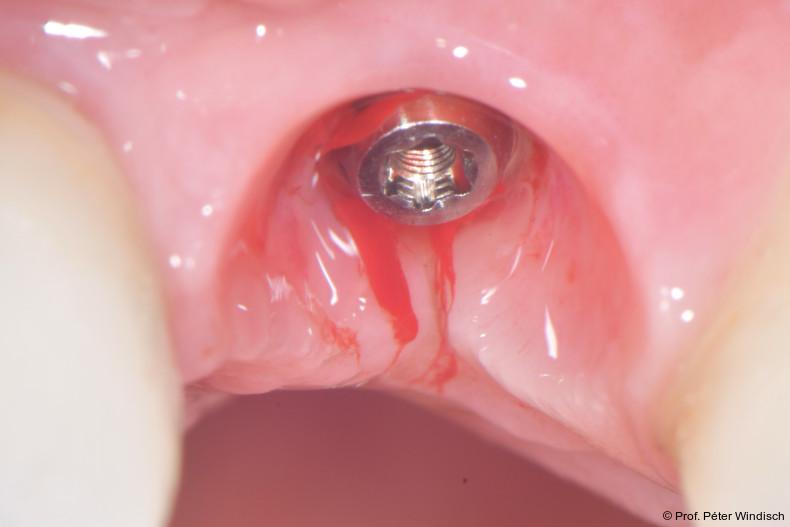

Radiologisch war ein signifikanter Knochenabbau um das Implantat zu verzeichnen (Abb. 2). Die klinische Untersuchung zeigte klassische Anzeichen einer periimplantären Entzündung: Bluten auf Sondieren (BOP+), erhöhte Sondierungstiefen (ST) und eine lokale Schwellung der Mukosa (Abb. 3–5). Das primäre Ziel war es, den Entzündungsprozess nicht chirurgisch zu stoppen und ein biologisches Milieu zu schaffen, das eine langfristige Stabilität ermöglicht. Der Implantataufbau wurde derzeit am Halsbereich zu dick ausgearbeitet und wies aus diesem Grund kein optimales Emergenzprofil auf. Nach der Eingliederung der definitiven prothetischen Versorgung kann es – insbesondere bei dicken suprakrestalen Weichgeweben – vorkommen, dass sich das Weichgewebe an die Kronenkontur adaptiert, was biologisch nicht immer gut toleriert wird. In der Folge kann es zu einer lokalen entzündlichen Reaktion kommen. Aus diesem Grund war zudem eine Umgestaltung der Krone vorgesehen.

Die erste Säule der Behandlung („Clean“-Phase) bildete die submarginale Instrumentierung unterstützt durch das Reinigungsgel. Da eine rein mechanische Reinigung oft nicht ausreicht, um den Biofilm in den Mikrostrukturen der Implantatoberfläche vollständig zu entfernen, wurde nach dem Entfernen der Krone adjuvant das Reinigungsgel (Perisolv) eingesetzt.

Nach einer Einwirkzeit von mindestens 60 Sekunden (Abb. 6) wurde die Tasche und die Implantatoberfläche gründlich mit Titanküretten instrumentiert. Während der Instrumentierung wurde das Reinigungsgel mehrmals in die Tasche appliziert und 60 Sekunden einwirken gelassen (ca. fünf bis sechs Mal), jeweils gefolgt von weiteren Instrumentierungszyklen. Dies wurde so oft wiederholt, bis keine sichtbaren Konkremente mehr aus der Tasche kamen (Abb. 7).